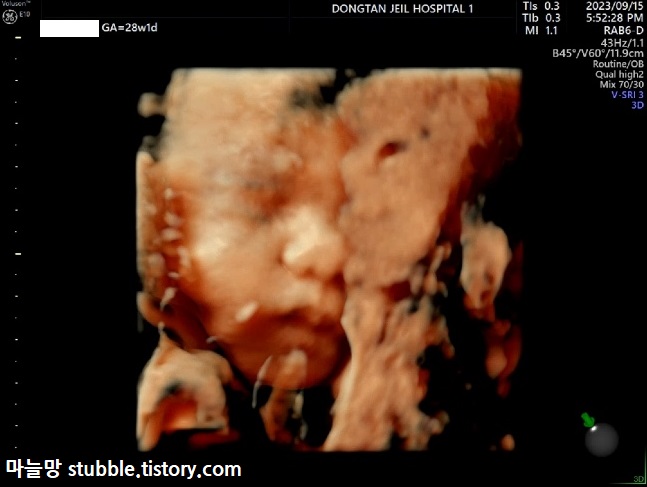

얼굴은 태반에 가려진 건지 코는 눌려서 나오고 반쪽얼굴만 겨우 확인할 수 있는 정도였어요.

믿어지지 않겠지만 이게 오늘 제일 잘 나온 입체초음파 사진입니다. 이것마저도 정확하진 않겠지만 그나마 얼굴이 다 나온 사진입니다. 복도를 5분 동안 걸어도 손과 팔이 얼굴로 향해있던 아가. 이제 얼굴 보려면 출생해서 봐야 할 것 같아요.